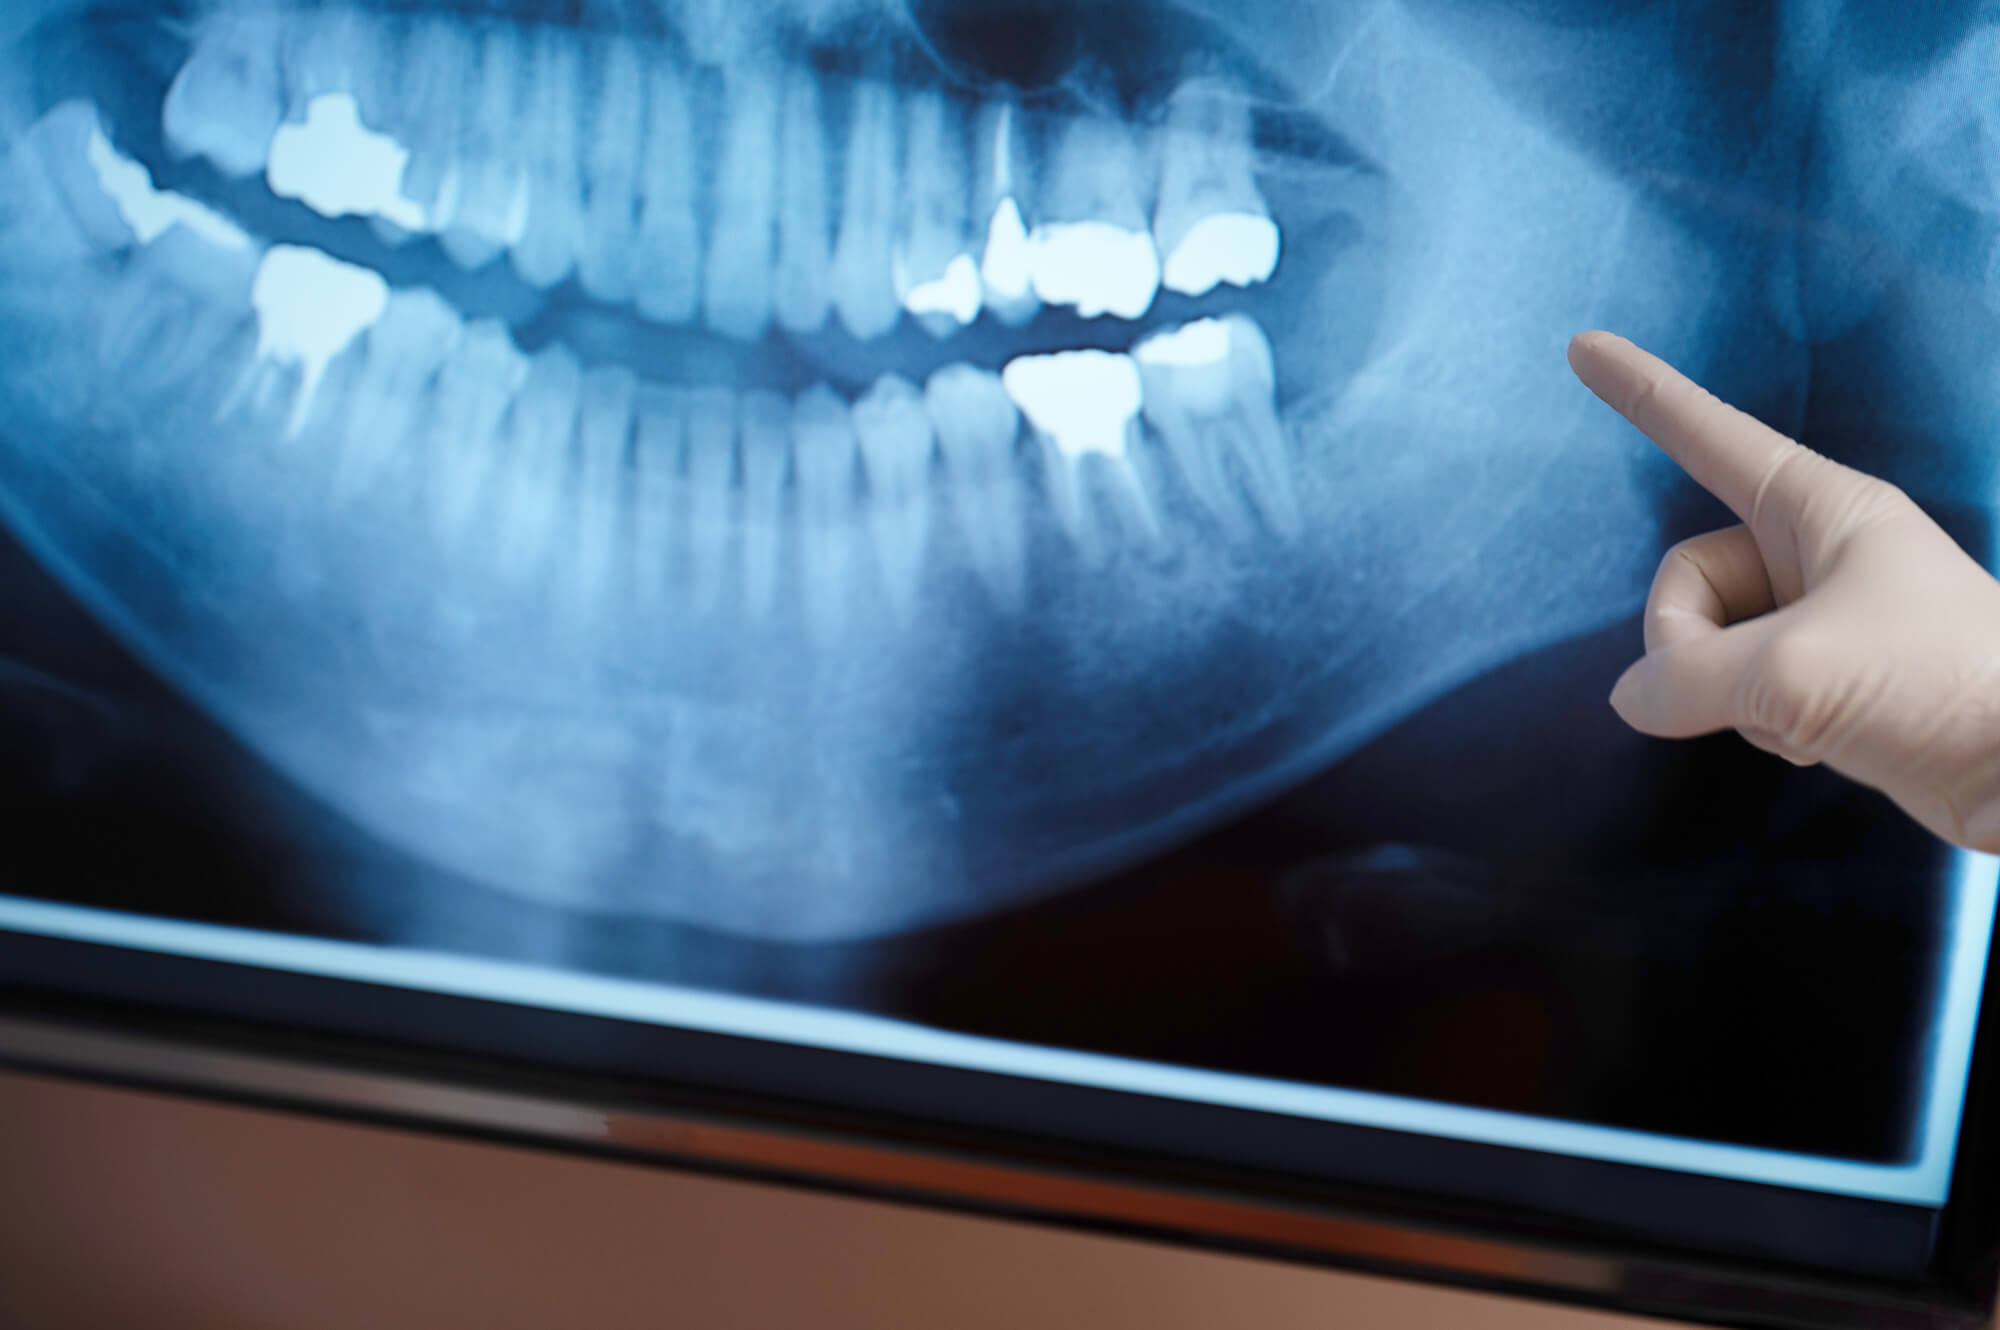

インプラント治療においては、事前にCT検査を行い、歯や骨の状態を精密に把握することが重要です。この検査により、神経や血管の正確な位置を把握でき、安全なインプラントの埋入位置を決定することが可能です。

しかし、CT検査による診断が不確実である、あるいは全く検査が行われないまま手術が進められる場合、神経損傷のリスクは高まるでしょう。

インプラント治療の成功には最新設備の有無が大きく影響します。特に神経損傷のリスクを減らすために欠かせないのが歯科用CTです。

この機器を用いることで、神経の位置を三次元で正確に把握し、安全な手術計画を立てることが可能になります。